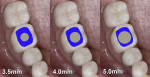

It can be challenging to replicate not only the crown portion of the tooth but also the entire tooth anatomy. The cross-section of teeth at the gingival margin have various shapes, such as triangular, rhomboidal, and ovoid, depending on the type of tooth it is (Figure 1). The challenge arises because implants are round in cross-section at the platform and the clinician needs to transition to the specific shape of the natural tooth to provide natural-looking esthetics that mimic the profile of the tooth. Selecting the optimal implant diameter for the space available is dependent on not only the mesial-distal dimension but also the buccal-lingual dimension.20,21 Use of an implant with a narrower diameter than the mesial-distal space available may complicate emergence profile and lead to proximal food traps and adversely affect esthetics (Figure 2). This has clinical relevance in both the anterior and posterior areas of the mouth.